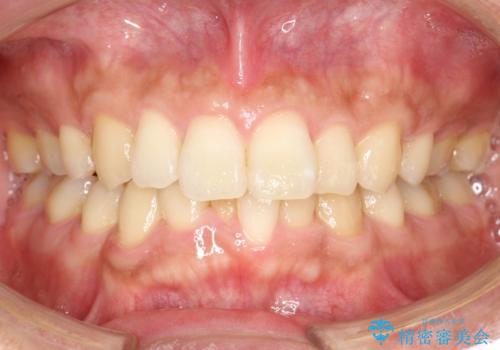

- 以前、上下左右4本抜いてワイヤー矯正をしていた方で、後戻りで下の前歯のガタガタを気にして来院されました。

マウスピース矯正にて、下の歯はIPR(歯と歯の間を削る)を入れることでガタガタの改善、咬み合わせの深さも改善をはかる治療計画をたてました。